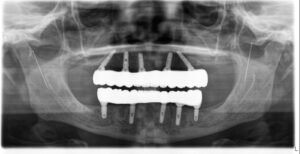

Yakından bakınca kişiselleştirme esastır. Kemik yoğunluğu, kalınlığı, dişeti profili, kapanış ilişkisi ve estetik beklenti kişiden kişiye değişir. 3D tomografi, dijital ölçü ve sanal cerrahi ile implantın yeri, açısı, boyu ve çapı kişiye özel belirlenir; protez tasarımı da buna göre planlanır. Bu yaklaşım hem doğal görünüm hem de uzun ömür sağlar.